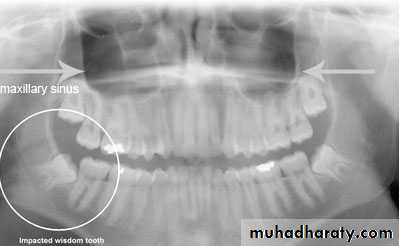

1- clinical inspection to disclose the missing tooth2- radiographic assessment showing the position of the unerupted tooth

b – periapical and occlusal filmc – panoramic view (OPG)

1- pell and Gregory according to the relation of the impacted tooth to the occlusal plane of the upper second molar2- the relation of the impacted upper third molar to the maxillary sinus

Relation of the impacted maxillary third molar to the maxillary sinus

Class A sinus approximation ( less than 2 mm bone between the antrum and the impacted tooth )Class B non sinus approximation ( more than 2 mm of bone exist between the impacted tooth and the sinus )